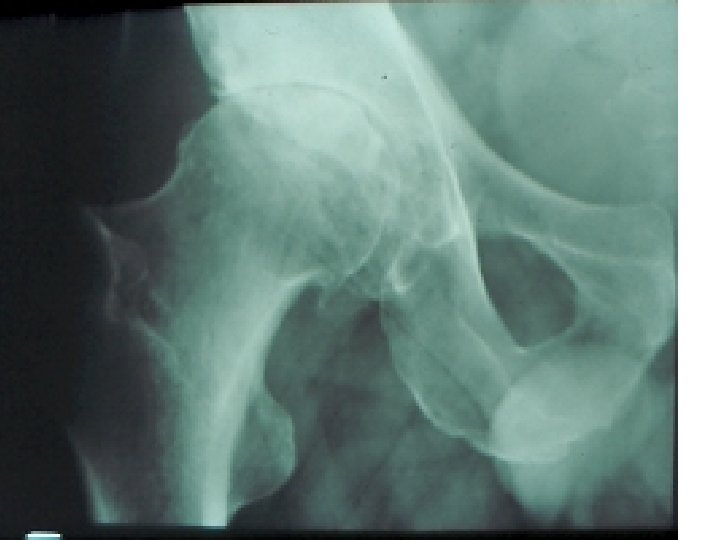

SEMIOLOGIE DE LA HANCHE J-P ESCHARD • Anatomie Articulation profonde Articulation très emboîtée mobilité

SEMIOLOGIE DE LA HANCHE J-P ESCHARD • Anatomie Articulation profonde Articulation très emboîtée mobilité réduite